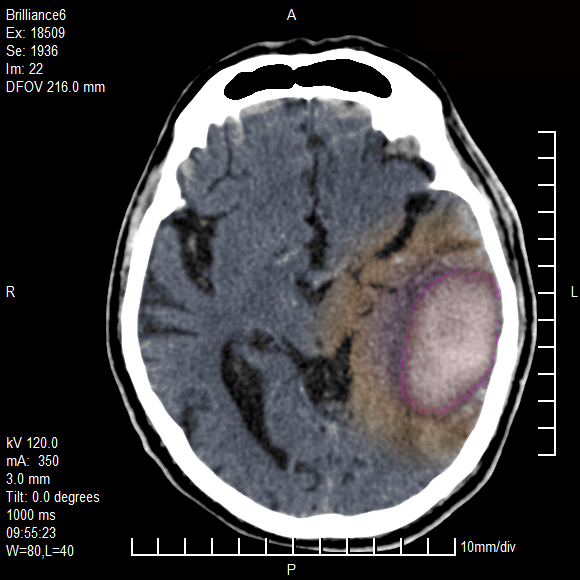

Αυτόματο ενδοεγκεφαλικό αιμάτωμα (κόκκινο περίγραμμα) με περιεστικό οίδημα (μπλέ). Αιμορραγία και στην αριστερή πλάγια κοιλία του εγκεφάλου (πράσινο βέλος). |